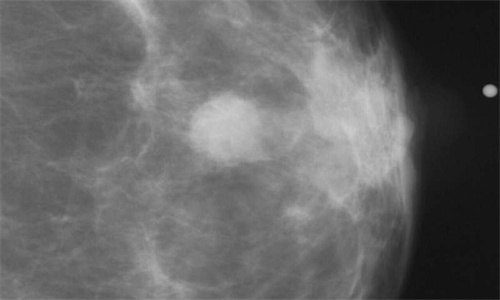

根据在北美放射学会(RSNA)年会上提交的研究,仅使用乳房x光图像生物标记开发的深度学习人工智能(AI)模型已经准确预测了导管原位癌(DCIS)和浸润癌。此外,该模型没有显示出对多个种族的偏见。传统的乳腺癌风险评估模型使用从患者问卷中获得的信息,如病史和生育史,来计算患者未来患乳腺癌的风险。

“在精准医疗领域,基于风险的筛查一直难以实现,因为我们无法准确评估女性患乳腺癌的风险,”该研究的主要作者、马萨诸塞州总医院(MGH)乳腺放射科医师Leslie R. Lamb说。“即使是现有的更好的传统风险模型在个体层面上也表现不佳。”

传统的风险模型在不同的患者种族中也表现不佳,很可能是由于用于开发模型的数据。兰姆博士说,“由于开发传统模型的人群不同,传统模型可能存在种族偏见。”“几个常用的模型主要是在欧洲高加索人群中开发的。”

根据美国癌症协会的数据,在所有种族和民族中,黑人女性的乳腺癌5年相对存活率更低。这意味着在所有乳腺癌类型中,黑人和白人妇女之间的5年生存率持续存在6%至8%的差异。为了准确确定乳腺癌风险,促进早期检测和提高患者存活率,开发适用于不同人群的风险模型是非常重要的。